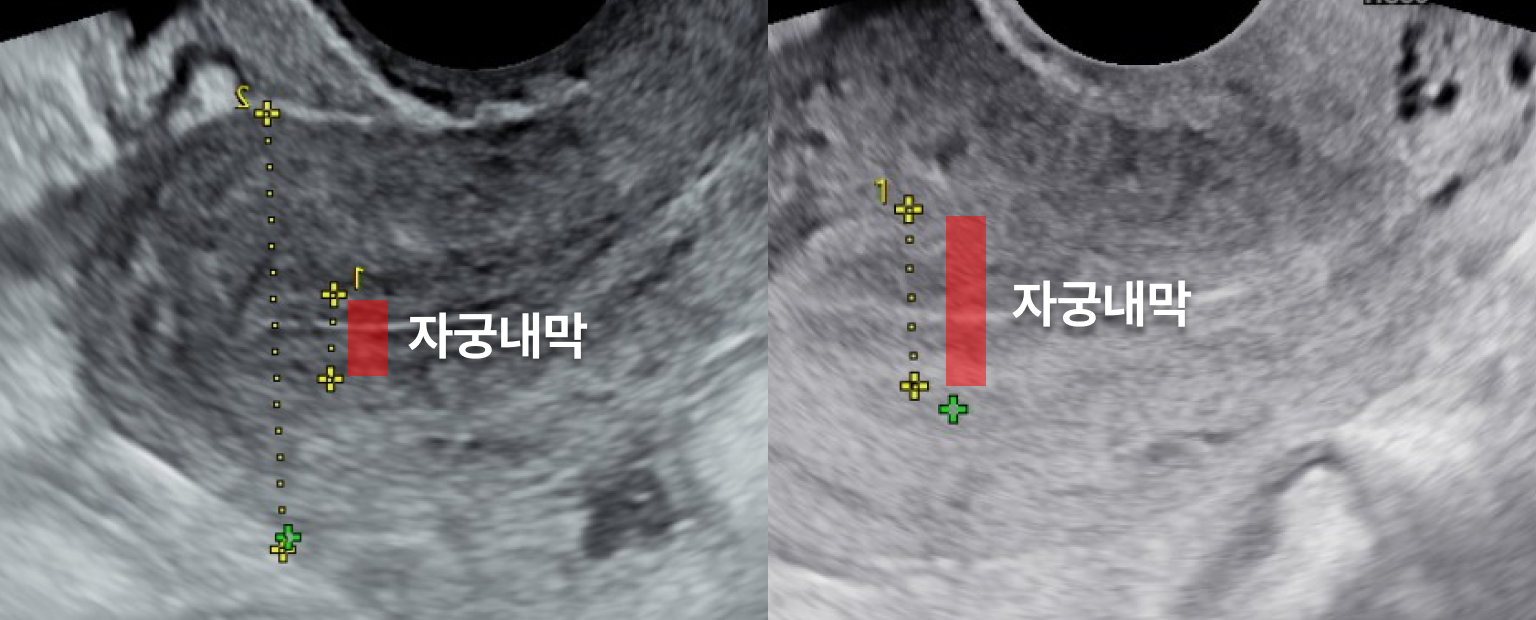

내막재생

Q.

원장님,

자궁내막이 얇다는 진단을 받았어요.

임신이 가능할까요?

네, 내막 재생 치료를 통해

충분히 임신 가능성을 높일 수 있습니다.

자궁내막두께가 얇아지면 배아의 착상이 어려워질 수 있습니다.

특히, 생리불순이 동반되는 경우 자궁내막 상태에 문제가 있을 가능성이 높습니다.

이와 함께 소파술이나 자궁내막염 같은 요인이 자궁내막을 손상하거나 얇아지게 만들 수 있습니다.

하지만, 이러한 문제도 적절한 치료와 관리를 통해 개선할 수 있습니다.

연세아이봄여성의원은 환자 개개인의 상태를 면밀히 분석한 뒤,

맞춤형 내막 재생 치료를 제공하여 착상 환경을 최적화하고, 임신 가능성을 높일 수 있도록 도와드립니다.